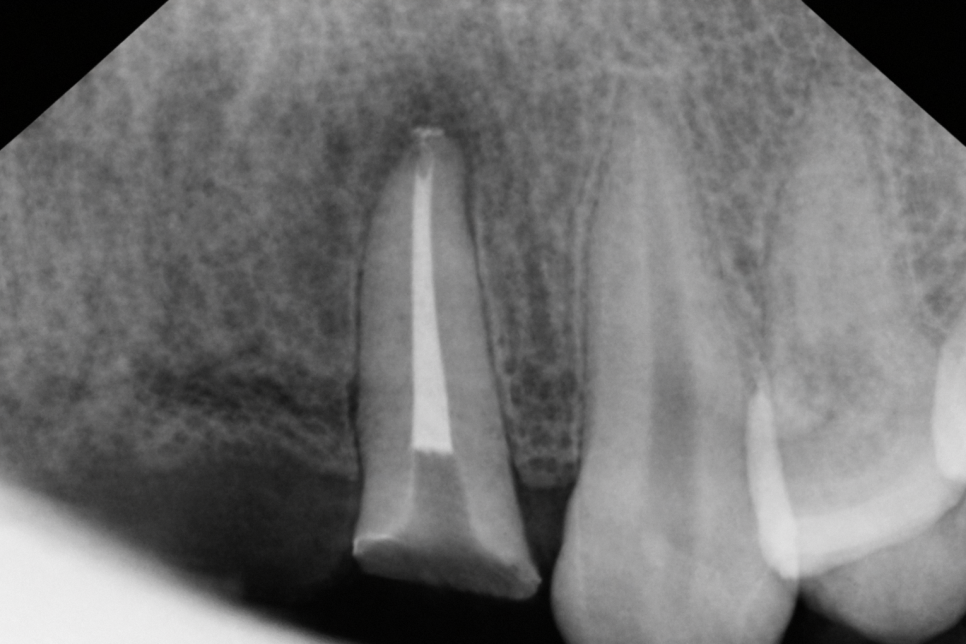

겉으로 보기엔 비슷한 파절도

진단해 보면 깊이가 다른 경우가 많습니다.

그러나 어느 층까지 깨졌느냐에 따라서

지금 느끼는 증상도 필요한 치료도 다릅니다.

처음에는 단순히 끝부분만 떨어져 나가도,

실제로는 미세한 균열이 깊어질 수 있습니다.

하지만 이 시간이 길어질수록

단순 수복으로 끝날 상황이

신경치료로 이어지는 경우가 생깁니다.

따라서 앞니 파절은 증상 여부보다는,

가능한 진단을 받아 보시는 것을 권장합니다.